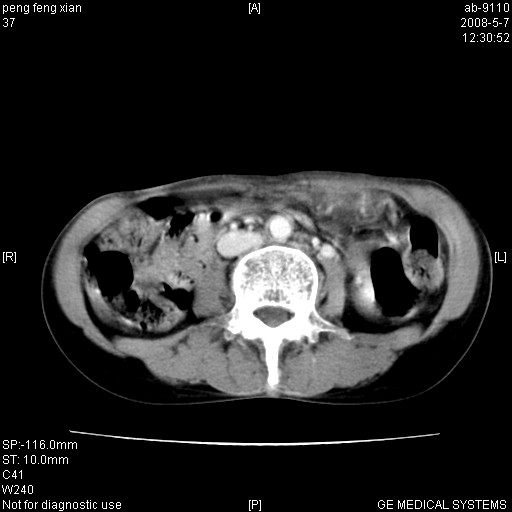

女,56岁。b超左一腹包块,考虑胃肠道肿瘤。

胃壁增厚,左前胸壁局限性隆起,考虑胃癌可能性大,建议做胃镜

典型胃癌胰体尾部受侵。

胃壁不规则增厚,考虑胃癌.应该多喝点水的.

胃体部胃壁增厚,不均匀性强化,与胰腺分解欠情.

考虑:胃癌,胰腺受侵待除外.

鉴别:胃淋巴瘤(强化不明显)

建议:胃镜检查.